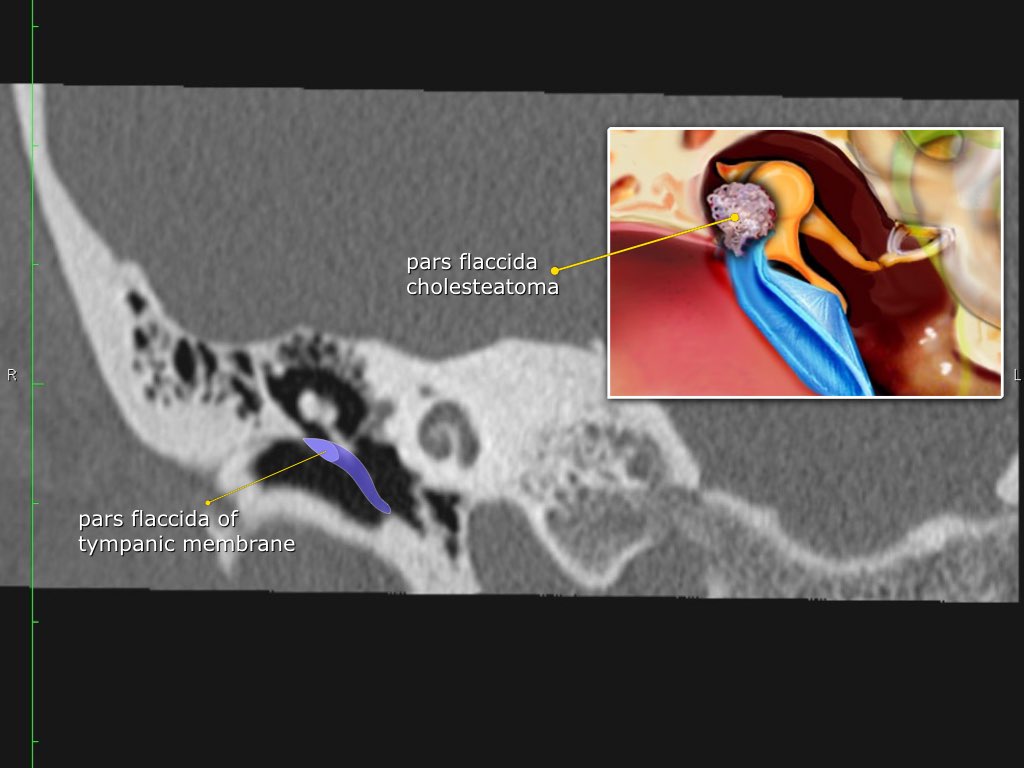

Pars flaccida là phần trên mỏng manh của màng nhĩ, liên quan đến rối loạn chức năng vòi nhĩ và cholesteatoma.

Hình ảnh một bệnh nhân có cholesteatoma.

Có một khối mô mềm ở vùng thượng nhĩ.

Đây thường là cấu trúc xương đầu tiên bị bào mòn do cholesteatoma, hình thành bởi sự co kéo vào trong của pars flaccida màng nhĩ vào vùng thượng nhĩ.